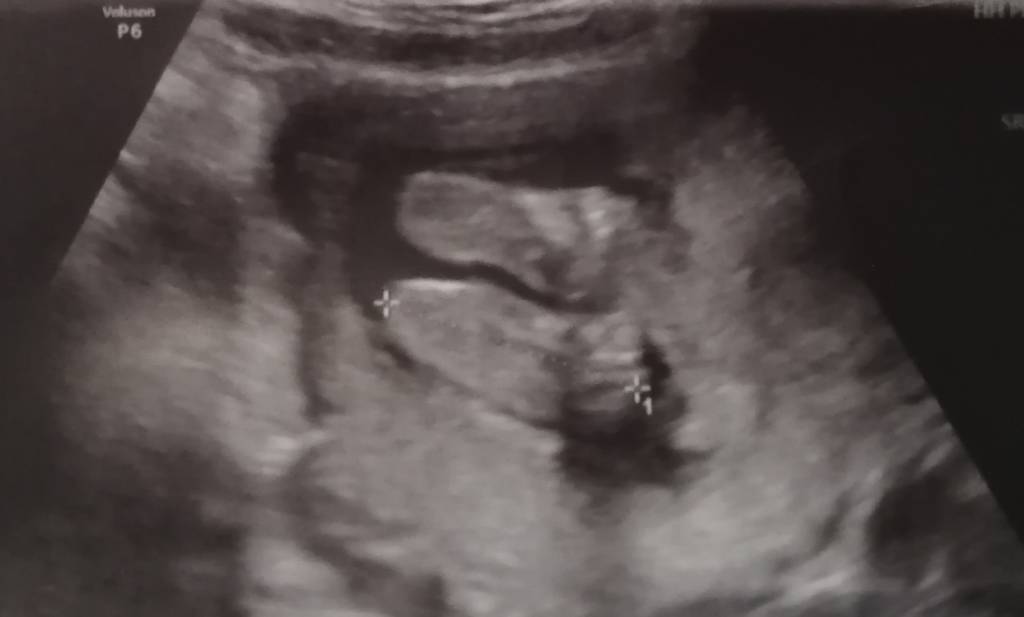

A ok ha ha ha nie zwróciłam uwagi [emoji23]Że jutro to pisałam wczoraj [emoji16] no mam nadzieję, że minie, bo mi mega zależy żeby podejrzeć co u maluszka [emoji849]

Może właśnie maluszek ciśnie Ci na żołądek. Daj znać jak po wizycie. Na którą masz?